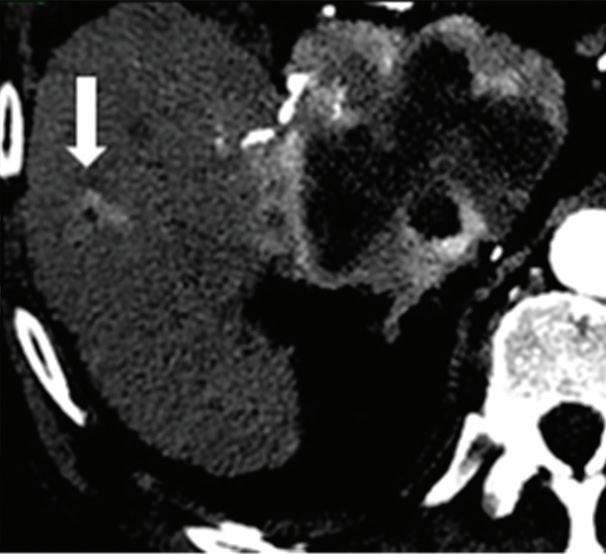

Renal and adrenal gland tumors. Contrast-enhanced-DECT images are particularly useful for the characterization of incidental renal or supra-renal lesions and for their follow-up, without the need of conventional unenhanced acquisition, translating into achieving a 30% mean dose savings for triphasic and up to 50% for biphasic renal protocols in daily clinical practice.17 It is also very useful in depicting hypervascular renal cell carcinoma metastasis in the liver or other sites, such as in the peritoneum and bowel wall (Figures 2 and 3).

Z effective

Spectral CT is able to generate Z effective images that show the mean atomic number of the material present in a voxel (Z effective values) and can be displayed as color coded overlay maps. Z effective images may be helpful to enhance the visual differences between different tissue types.46 Furthermore, due to the high atomic number of iodine compared to other tissues present in the human body, the Z effective images can highlight enhancing structures (Figures 2, 3, 4, and 5) and could be used for quantitative analysis to differentiate benign from malignant tumors or lymph nodes.16,45,47

Effectiveness of spectral CT imaging for detection of hypervascular liver metastases. A small hypervascular metastasis (arrow) from renal cell carcinoma. (a) Axial contrast-enhanced conventional CT image obtained in the arterial phase, corresponding (b) monoenergetic 50 keV, and (c) Z effective image.

Liver tumors. Use of low-monoenergetic images on late arterial phase improves the detection of hypervascular liver lesions (e.g., HCC in cirrhotic liver) (Figure 4).3,17,52,53 It also improves detection of hypovascular liver metastases on portal-venous-phase.54